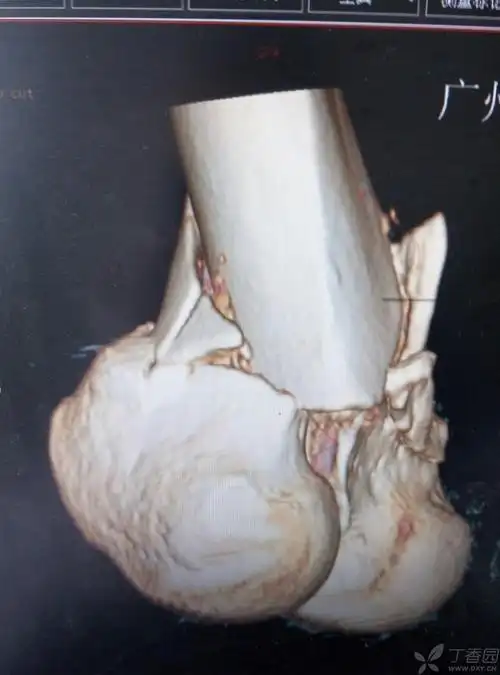

股骨髁骨折 - 骨科专业讨论版 -丁香园论坛

股骨髁骨折(附一骨科谢昀)